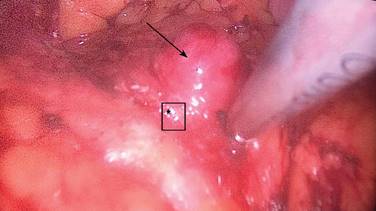

Se trata de un paciente femenino de 51 años de edad sin antecedentes familiares de importancia. Inicia con el padecimiento tres años previos a su ingreso al referir episodios intermitentes de diaforesis, palpitaciones, se valora con glicemia capilar en 28 mg/dl, presenta además cefalea de tipo opresiva de localización frontal, intensidad 5 de 10 en la escala visual análoga, mejora su sintomatología tras la administración de solución intravenosa o alimentos ricos en glucosa. Dos años después se presenta con crisis convulsiva por lo cual acude a valoración, a la exploración física: de edad aparente a la cronológica, tórax sin alteraciones, abdomen globoso a expensas de panículo adiposo, blando depresible no doloroso a la palpación, peristalsis presente y normal, el resto de la exploración sin datos patológicos. Sus estudios paraclínicos muestran hemoglobina glucosada en 4.5%, sulfonilureas en sangre negativas, glicemia de ingreso 37 mg, insulina en 64.1 UI/ml, péptido C en 8.36 ng/ml, TSH 1.8 UI/ml, T4L 1.11 ng/dl, los resultados de la tomografía axial computarizada (TAC) de abdomen contrastado se reportaron normales. En la resonancia magnética nuclear (RMN) aparece una lesión nodular entre la cabeza y el cuerpo del páncreas de 2.0 x 1.8 x 1.6 cm, la cual no condiciona obstrucción. Se procede a realizar ultrasonido endoscópico (Figura 1) corroborando la localización superficial del tumor, se encuentra a más de 2 mm de los vasos esplénicos y del conducto pancreático. Debido al tamaño y localización se procede a realizar enucleación laparoscópica del insulinoma. Se induce neumoperitoneo, se colocan puertos en cicatriz umbilical de 10 mm, otro puerto para el retractor hepático en línea anterior axilar derecha de 10 mm, dos puertos izquierdos y uno derecho de 5 mm. Se continúa con la disección del omento gastrocólico, se levanta la cámara gástrica y se observa la tumoración entre el cuello y cola del páncreas (Figura 2). Se realiza enucleación con bisturí armónico y se extrae de la cavidad abdominal con bolsa por el puerto del ayudante.

Figura 2: Enucleación de insulinoma por laparoscopia. Se observa el insulinoma (flecha) entre la cabeza y cuerpo del páncreas (asterisco).